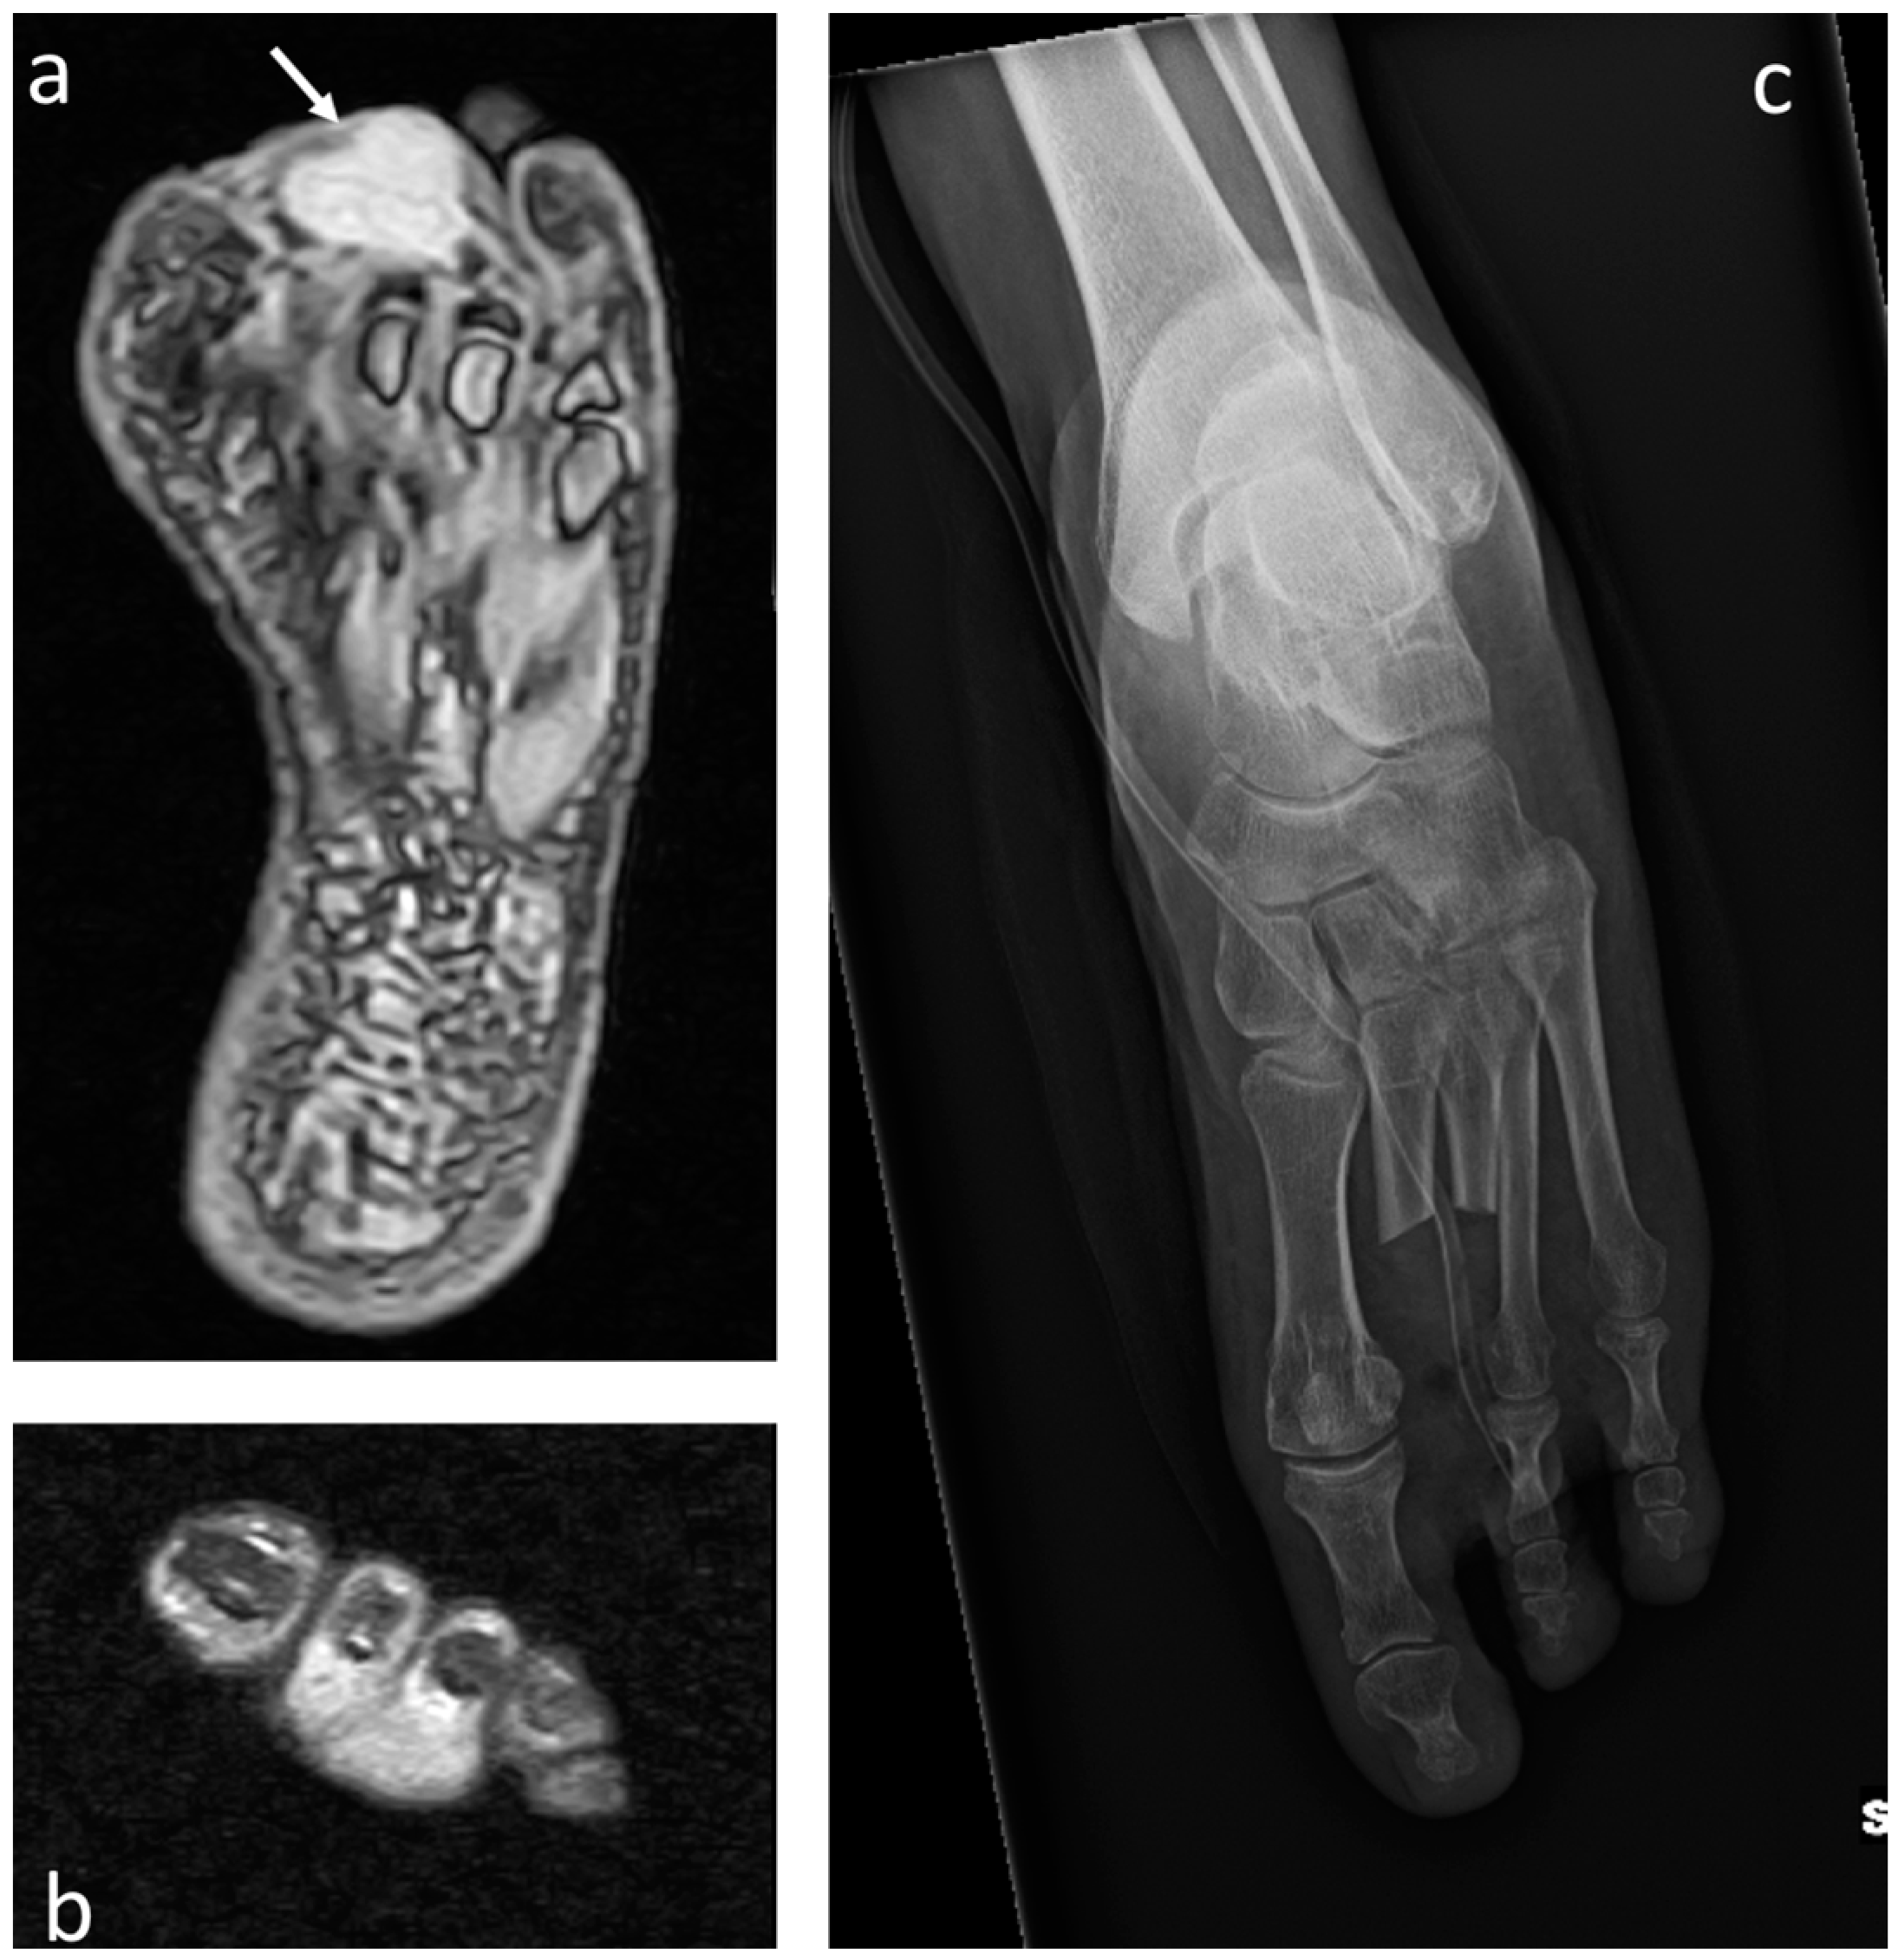

3.1. Osteosarcoma

3.2. Chondrosarcoma

3.3. Ewing Sarcoma

3.4. Acrometastases